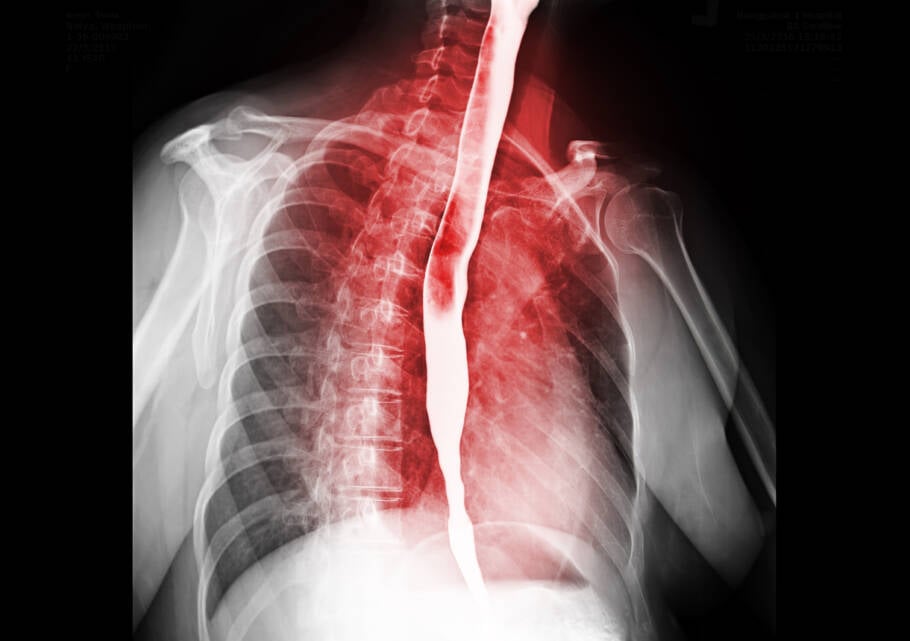

O câncer de esôfago é uma neoplasia maligna que afeta o tubo muscular responsável por conduzir alimentos da boca ao estômago. Globalmente, é o oitavo tipo de câncer mais frequente. No Brasil, as estimativas para o triênio 2023-2025 apontam para 10.990 novos casos anuais de câncer de esôfago, conforme dados do Instituto Nacional de Câncer (INCA).

Quais são os sintomas do câncer de esôfago?

Alguns dos principais sintomas do câncer de esôfago são perda de peso e dificuldade para engolir.